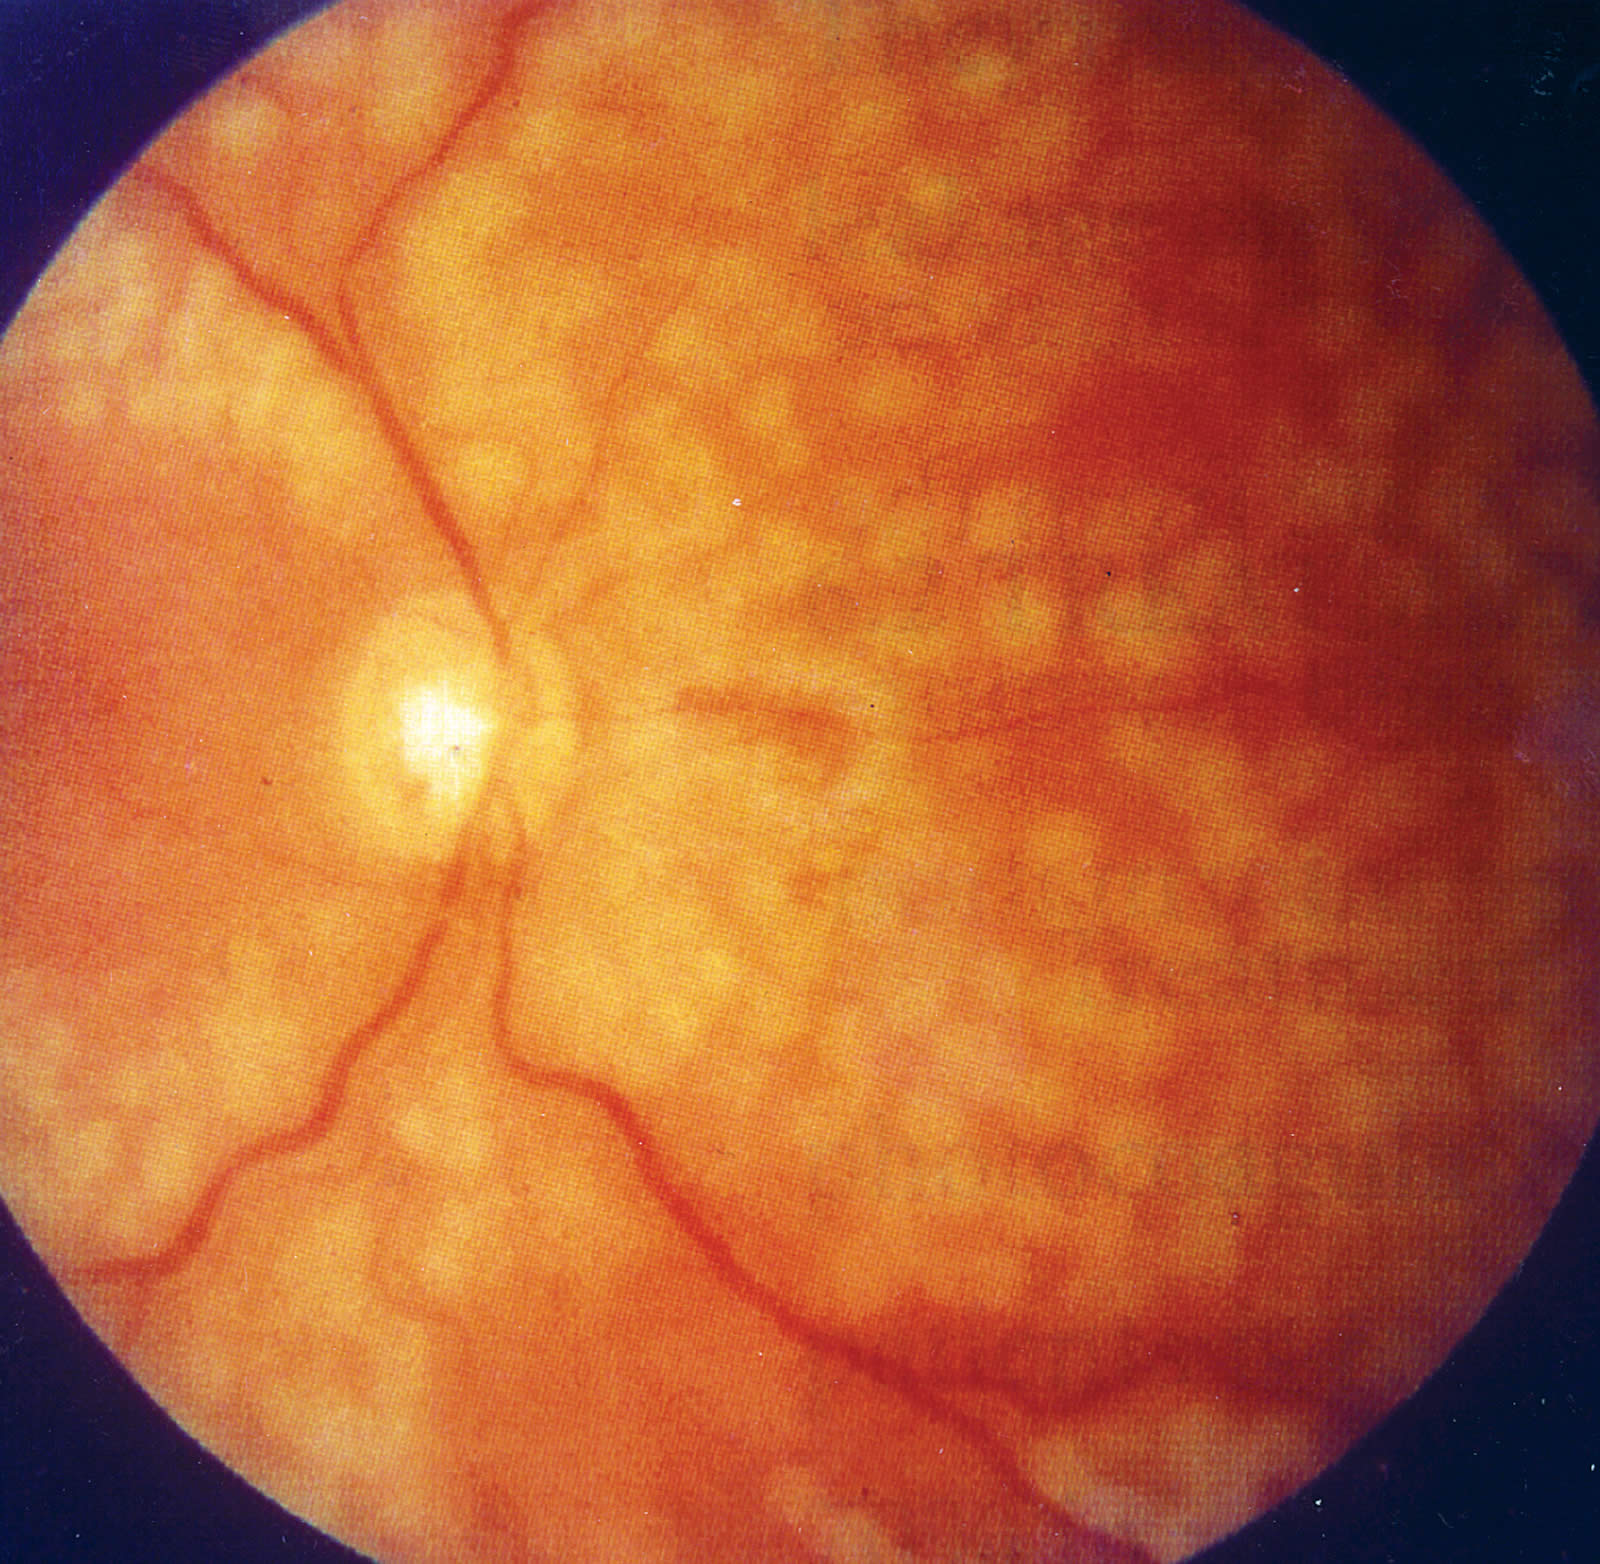

The following photographs show examples of proliferative diabetic retinopathy (PDR).

- PDR with NVE (Figure 3).

- PDR with NVD (Figure 4).

Proliferative diabetic retinopathy (PDR)

Micro-vascular pathology with capillary closure in the retina leads to hypoxia of tissue. The hypoxia leads to release of vaso-proliferative factors which stimulate new blood vessel formation to provide better oxygenation of retinal tissue. These new vessels growing on the retina are called neovascularisation elsewhere (NVE) and those on the optic disc are called neovascularisation of the disc (NVD). These new vessels can bleed and produce haemorrhage into the vitreous.